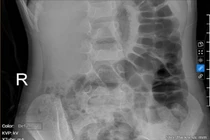

Bé gái 5 tuổi bị táo bón kéo dài gây tiểu dầm hàng đêm

Tình trạng táo bón mạn tính ở trẻ có thể chèn ép bàng quang, gây tiểu dầm, tiểu rắt và rối loạn tiểu tiện, cần chẩn đoán và điều trị kịp thời.

Tình trạng táo bón, ứ phân kéo dài có thể chèn ép bàng quang gây tiểu dầm

Bệnh viện Đa khoa Medlatec vừa thăm điều trị cho bé T.H.B.H., 5 tuổi mắc chứng tiểu dầm từ nhỏ.